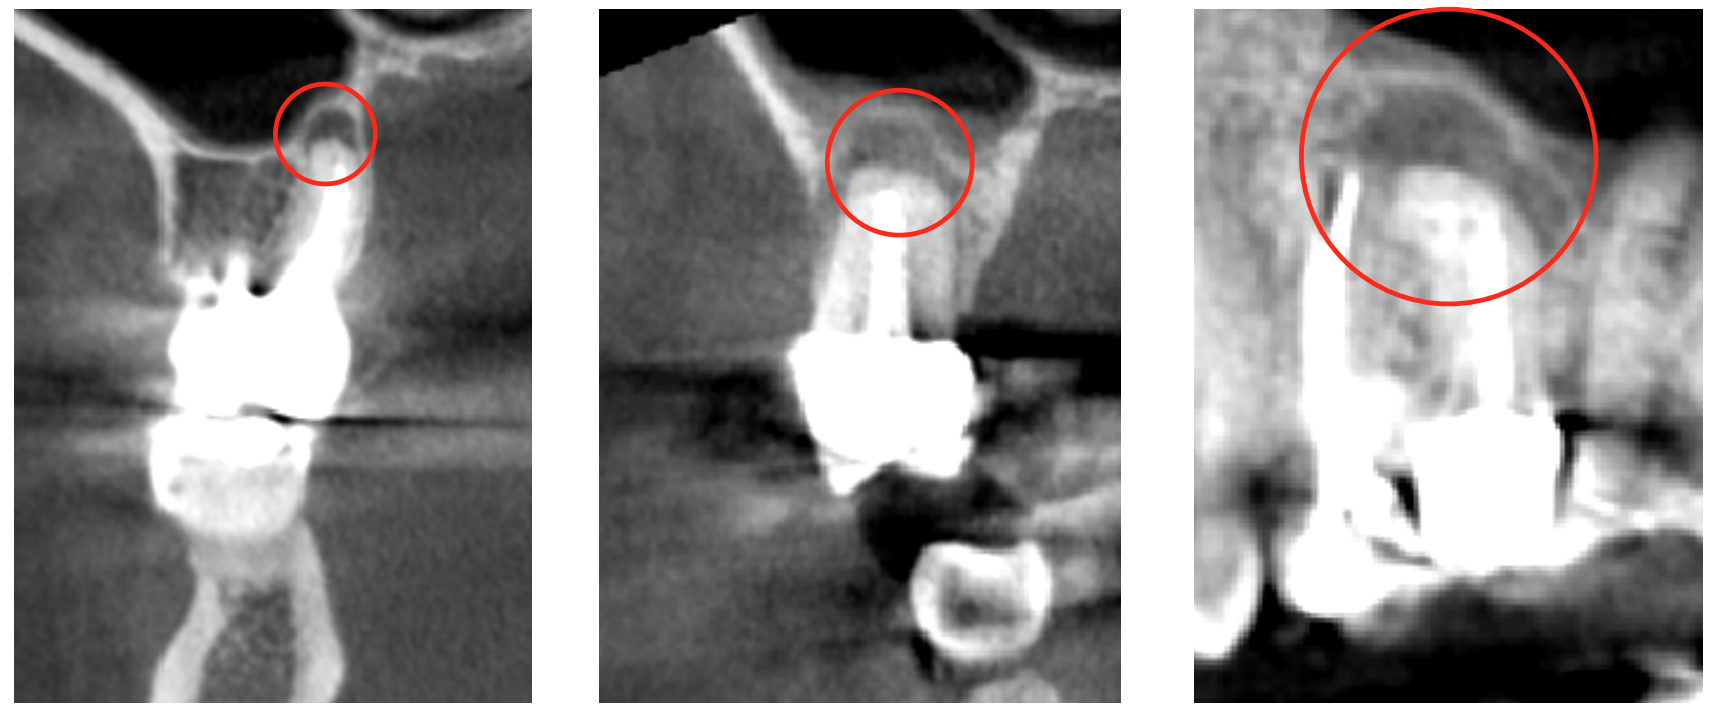

NICO (neuralgia inducing cavitational osteonecrosis), FDOK (fettig degenerative Osteolyse im Kiefer) oder auch aseptische Knochennekrose genannt, ist eine vielfach unerkannte hohlraumbildende Art von Entzündung im Kiefer. Der Verlauf ist meist in der eigentlichen Region asymptomatisch und chronisch weshalb sie meist nur als Zufallsbefunde entdeckt werden. Der chronische Verlauf als sog. "silent inflammation“ stellt für den Körper ein Störfeld im Sinne eines neuromodulativen Triggers dar und sollte deshalb immer behandelt werden.

Die Entstehung von NICOs ist noch nicht sicher geklärt. Vielfach wird von aseptischen (keimfreien) Knochen-Nekrosen geschrieben, die nach Durchblutungsstörungen (Infarkten) im Kieferknochen entstehen. Der betreffende Knochenbezirk stirbt ab und es bilden sich Hohlräume, gefüllt mit fettig degeneriertem Gewebe mit fettiger Flüssigkeit (Ölaugen), gestörten Zellen und Ansammlungen von Bakterien und Schwermetallen.

NICOs treten vor allem nach Zahnentfernungen auf. Insbesondere dann, wenn sich der Patient in einem Nährstoffmangelzustand befindet und während der Operation kein spezielles Regenerationsprotokoll verwendet wird (Piezosurgery, Ozon und Choukroun-APRF, Ernährungsprotokoll). Ebenfalls kommen NICOs häufig im umliegenden Gewebe von wurzelkanalbehandelten Zähnen vor. NICOs sind in der Region selbst häufig sogar gänzlich schmerz- und reizlos und manifestieren sich eher systemisch.

Links: eröffnete Situation, brauner, fettiger Knochen (Quelle: swiss-biohealth.com), Mitte: gesunder Knochen und NICO Knochen bei einem Humanpräparat (Quelle: swiss-biohealth.com), Rechts: Histologische Nachweise der entzündlichen Infiltrate Quellen: Bild oben: Lechner J. Aseptic-avascular osteonecrosis: local "silent inflammation" in the jawbone and RANTES/CCL5 overexpression. Clin Cosmet Investig Dent. 2017 Nov 9;9:99-109. doi: 10.2147/CCIDE.S149545. eCollection 2017 und Bild unten: Prof. Wainwright, Kavitätenbildende Osteonekrosen des Kieferknochens – Mythos oder Realität?